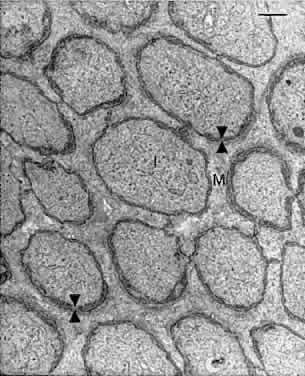

As described above, a thin membrane is apparent at the level of the photoreceptor inner segments (see Fig. 5B). This so-called membrane is actually a series of intermediate junctions (zonulae adherentes) between the rod and cone inner segments and the apical processes of the Müller cells (Figs. 12 and 13). These junctions constitute the inner border of the subretinal space and are a barrier to diffusion of large molecules into and out of this space.7

Fig. 12. The external limiting membrane is formed by continuous bands of intermediate junctions (zonulae adherentes) seen here in meridional section. The inner segments (I) of the photoreceptors are linked to Müller cell processes (M) by the intermediate junctions (arrowheads). Bar = 0.5 μm. (Hogan MJ, Alvarado JA, Weddell JE: Histology of the Human Eye. Philadelphia: WB Saunders, 1971.)

Fig. 13. A tangential section through the external limiting membrane of human retina. Note continuous belts of intermediate junctions (arrowheads) between the photoreceptor inner segments (I) and Müller cell processes (M). Bar = 1.0 μm. (Hogan MJ, Alvarado JA, Weddell JE: Histology of the Human Eye. Philadelphia: WB Saunders, 1971.)